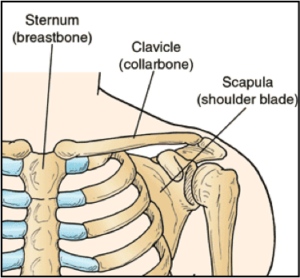

The Clavicle is part of your shoulder and connects your rib cage to your arm.

The Clavicle lies above several important nerves and blood vessels. However, these vital structures are rarely injured when the Clavicle breaks, even though the bone ends can shift when they are fractured.

The clavicle is a long bone and most breaks occur in the middle of it. Occasionally, the bone will break at its ends, where it attaches at the ribcage or Shoulder blade.